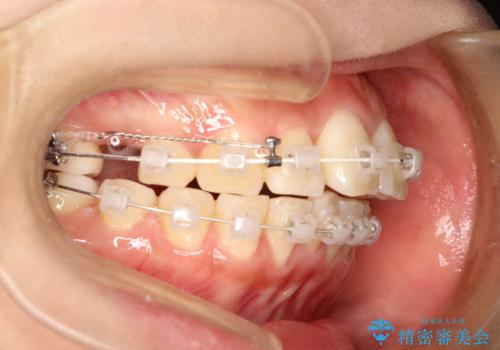

- 上の前歯が出てて、前歯で咬めないとのことで来院されました。

上顎の歯を1本抜歯して、前歯のガタガタと、前方に出ているのを改善する計画としました。

上下の前歯の距離が近くなり、前歯で咬みやすくなり、審美的にも改善できました。